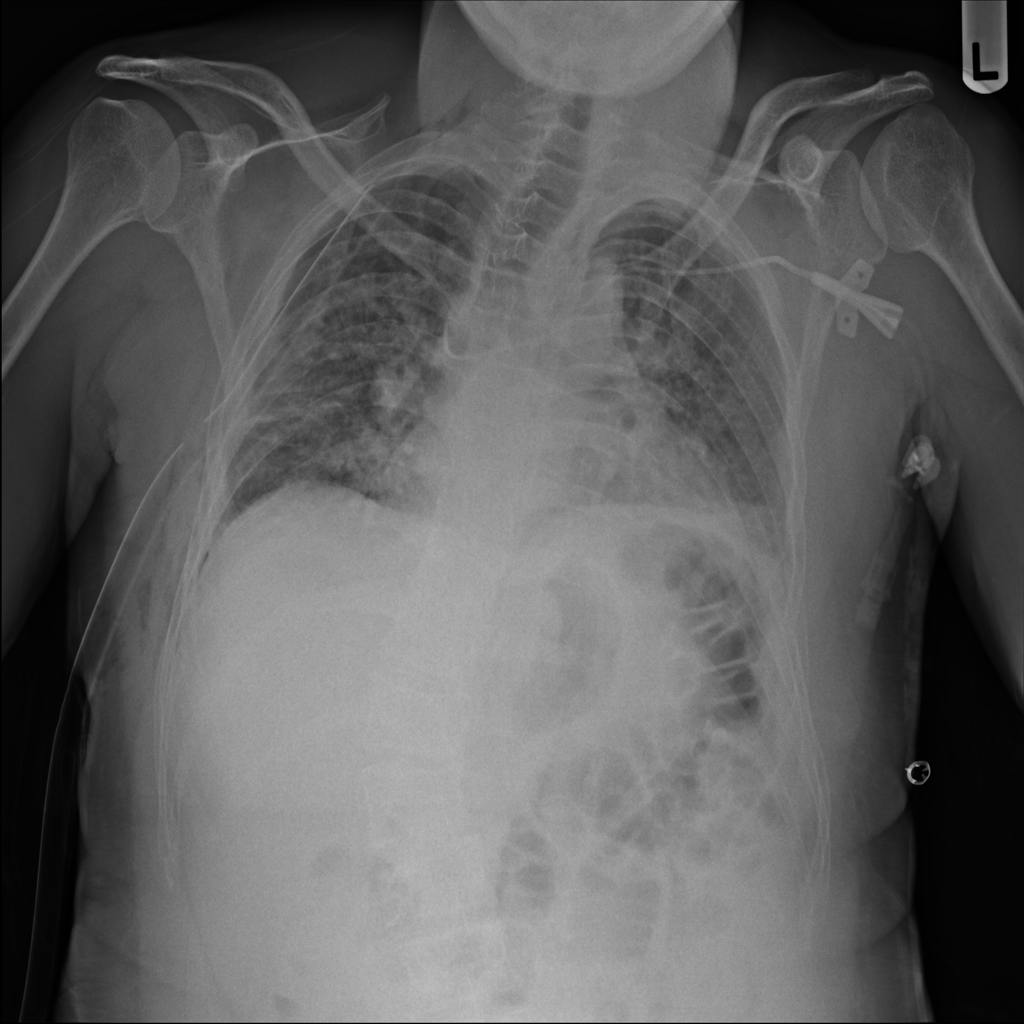

Showing up to 90 reference images for Pneumothorax.

PAT-4639 · IMG-011Pneumothorax

PAT-4639 · IMG-011

AP